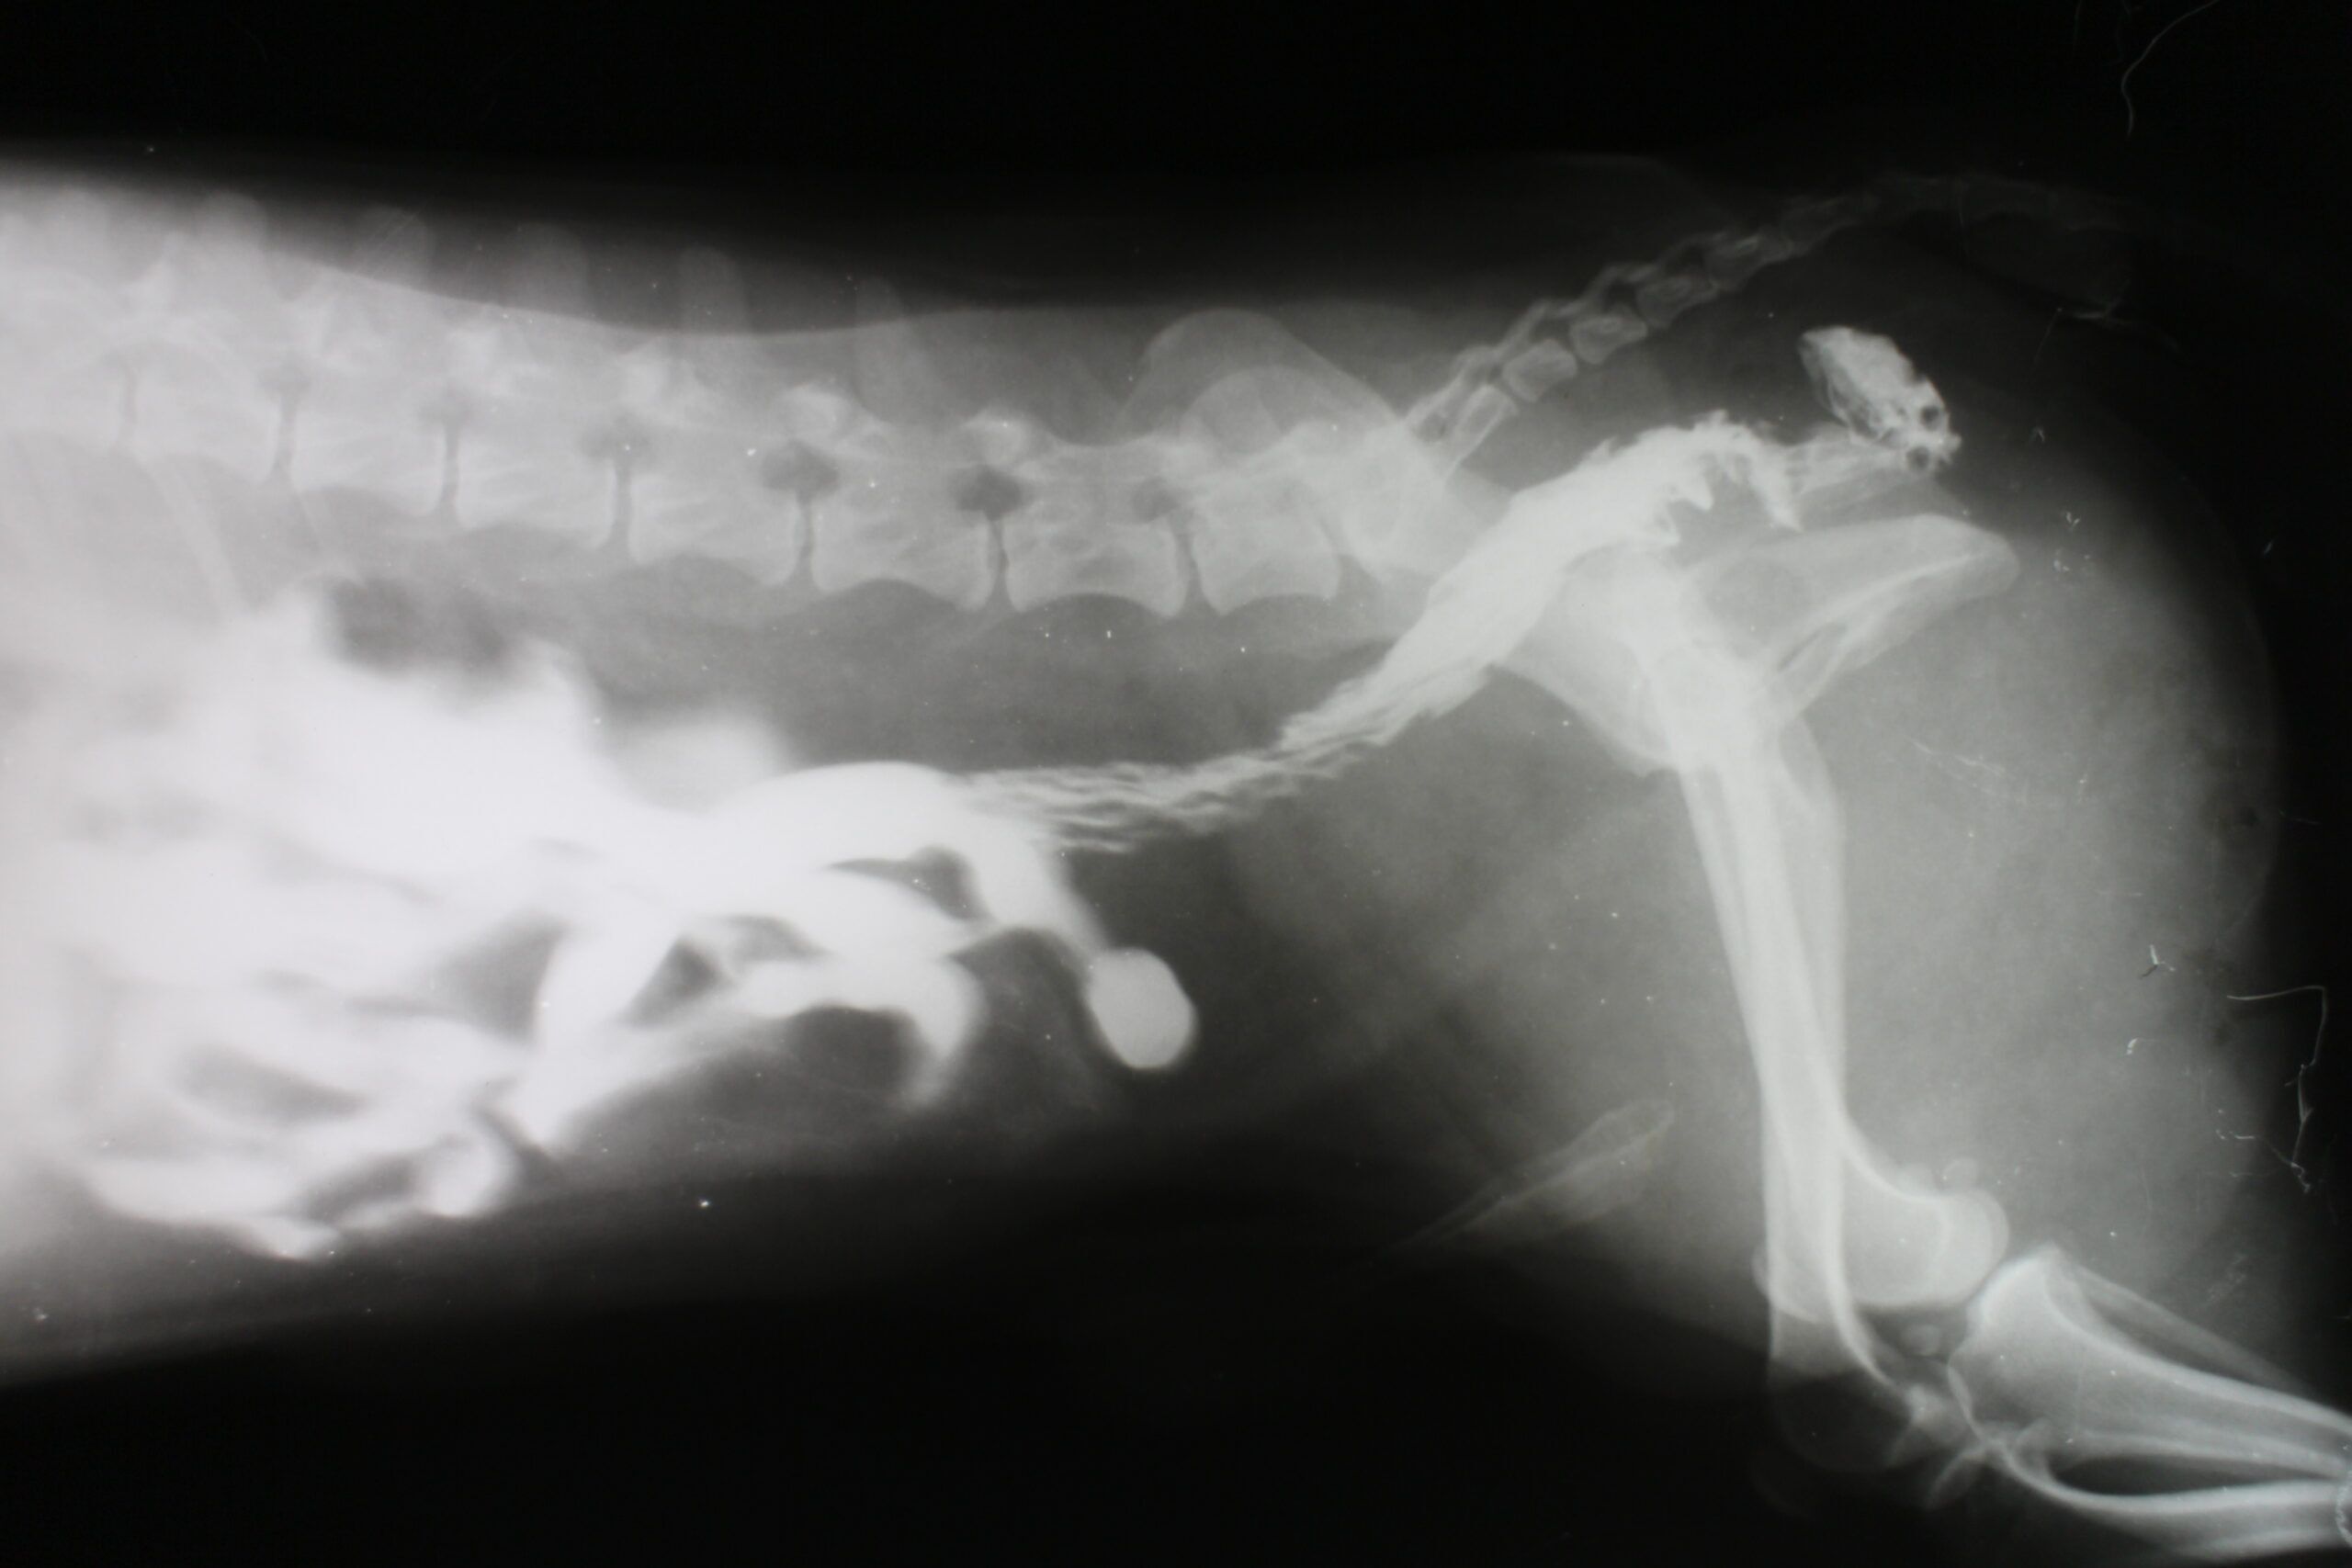

- X-rays. X-rays can be performed to get a look at the inner ear. This allows vets to see if there is an obstruction or inflammation inside the pet’s ears.